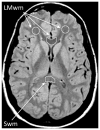

Performance on measures of cognitive processing speed (CPS) slows with age, but the biological basis associated with this cognitive phenomenon remains incompletely understood. We assessed the hypothesis that the age-related slowing in CPS is associated with myelin breakdown in late-myelinating regions in a very healthy elderly population. An in vivo magnetic resonance imaging (MRI) biomarker of myelin integrity was obtained from the prefrontal lobe white matter and the genu of the corpus callosum for 152 healthy elderly adults. These regions myelinate later in brain development and are more vulnerable to breakdown due to the effects of normal aging. To evaluate regional specificity, we also assessed the splenium of the corpus callosum as a comparison region, which myelinates early in development and primarily contains axons involved in visual processing. The measure of myelin integrity was significantly correlated with CPS in highly vulnerable late-myelinating regions but not in the splenium. These results have implications for the neurobiology of the cognitive changes associated with brain aging.